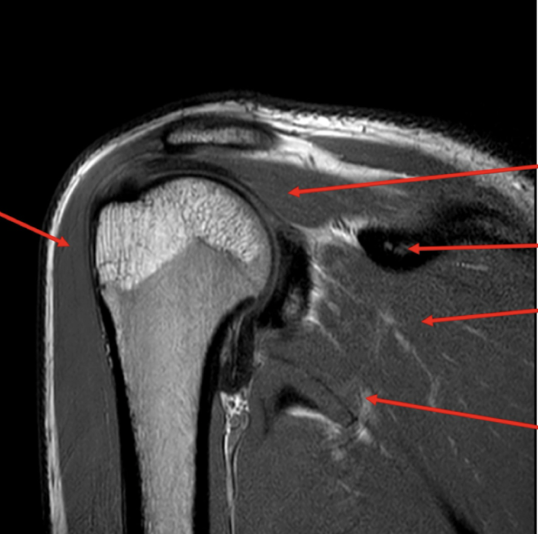

Sequence + pathology?

• PD, PDFS

• Path = supraspinatus tendon tear

• -  You can follow the tendon and see that it stops just above the humeral head rather than

attaching to the lateral aspect of the head.

• -  More prominent of the PDFS you can see high signal around the lateral aspect of the humerus

indicative of a pathological process occurring because of the tear.